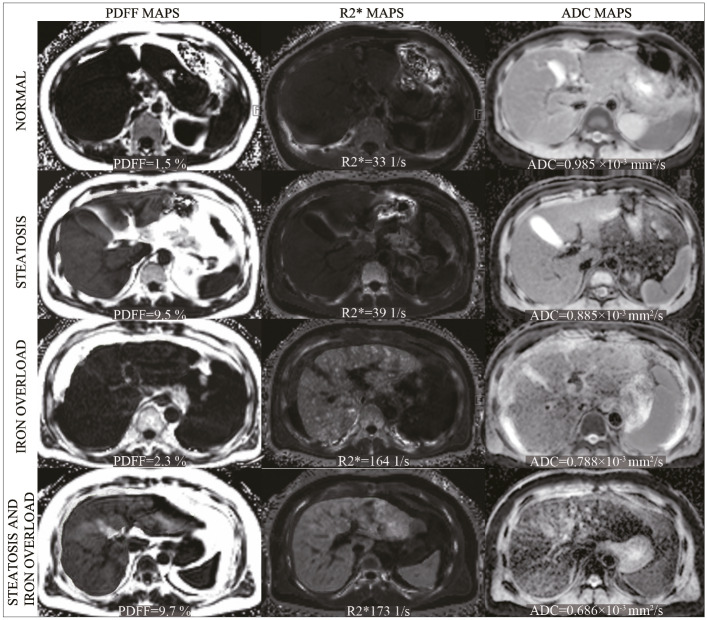

Methods: Seventy-three patients with chronic hepatitis B (CHB) were included in this retrospective study. The aspartate aminotransferase-to-platelet ratio index (APRI) was calculated for classification of the fibrosis grade. Significant fibrosis and cirrhosis were diagnosed with the APRI. The proton density fat fraction (PDFF), R2*, and ADC values were measured. The impact of the PDFF and R2* on the ADC was analyzed. The PDFF- and R2*-corrected ADC values (ADCPDFF and ADCR2*) were calculated according to linear regression equations. The diagnostic performance of uncorrected ADC (ADCu), ADCPDFF and ADCR2* in predicting significant fibrosis and cirrhosis was assessed, and the area under the curve (AUC) values were compared.

Results: Among the 73 patients in this study, the mean ADC was 0.866 ± 0.084×10-3 mm2/s, the mean R2* was 60.24 (42.77, 85.37) 1/s, and the mean PDFF was 2.90% (1.60%- 4.80%). The ADC was negatively correlated with the PDFF (r= -0.298, P = .010) and R2* (r = -0.457, P < .001). Linear regression analysis showed that the PDFF and R2* were independent factors of the ADC (β= -0.315, P = .007, R2= 0.099 and β= -0.493, P < .001, R2= 0.243, respectively). Compared with the uncorrected ADC (r= -0.307, P = .022), the correlation between the ADCPDFF and fibrosis grade increased (r= -0.513, P < .001), and the correlation between the ADCR2* and fibrosis grade decreased (r=-0.168, P = .215). The AUC of the ADCPDFF was significantly larger than that of the ADCu in the diagnosis of significant fibrosis and cirrhosis, which increased from 0.68 to 0.81 (P = .003) for predicting significant fibrosis and from 0.75 to 0.84 (P = .009) for predicting cirrhosis. The AUCs for the ADCR2* in the diagnosis of significant fibrosis and cirrhosis were both lower than that for the uncorrected ADC (P = .206 and P = .109, respectively).